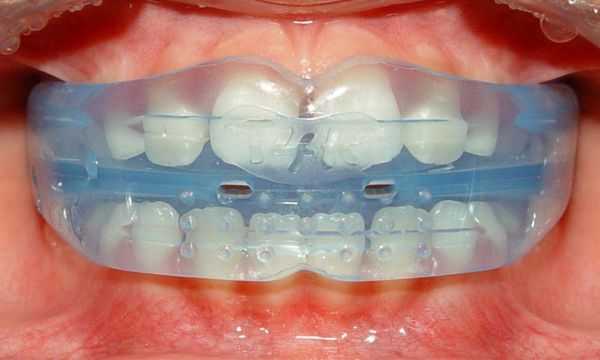

Детям в возрасте 5-12 лет, имеющим неправильный прикус, может быть рекомендовано ношение преортодонтического трейнера - функционального аппарата из эластичного силикона. Удобство трейнеров заключается в том, что они используются только во время сна и 1 час в течение дня; при этом эффективно воздействуют на мышцы и зубочелюстную систему, отучают детей от вредных оральных привычек.

После 6 лет в лечение глубокого прикуса у детей включают: каппы, ретейнеры, съемные пластинки вестибулярного типа и иные устройства. Инструкция по ношению в каждом случае индивидуальная.